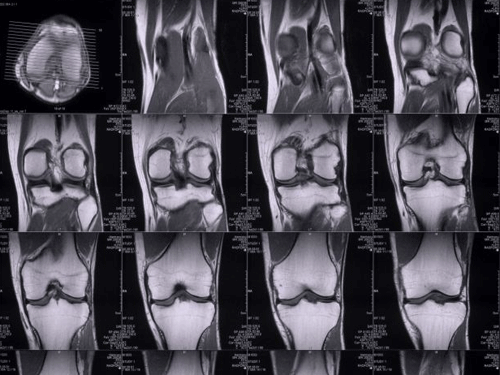

Nghiên cứu của các nhà khoa học Mỹ cho thấy có thể xác định nhân thân con người qua hình ảnh quét cộng hưởng từ (MRI) của xương đầu gối như một công nghệ mới phục vụ kiểm tra an ninh tại sân bay.

TS Lior Shamir và các cộng sự tại Đại học Công nghệ Lawrence (Mỹ) đã phân tích chỉ số sinh trắc học mẫu MRI đầu gối của 2.686 người và nhận ra họ với độ chính xác lên tới 93%.

Nhóm nghiên cứu cho rằng mỗi người có đặc trưng xương đầu gối riêng biệt - Ảnh Daily Mail